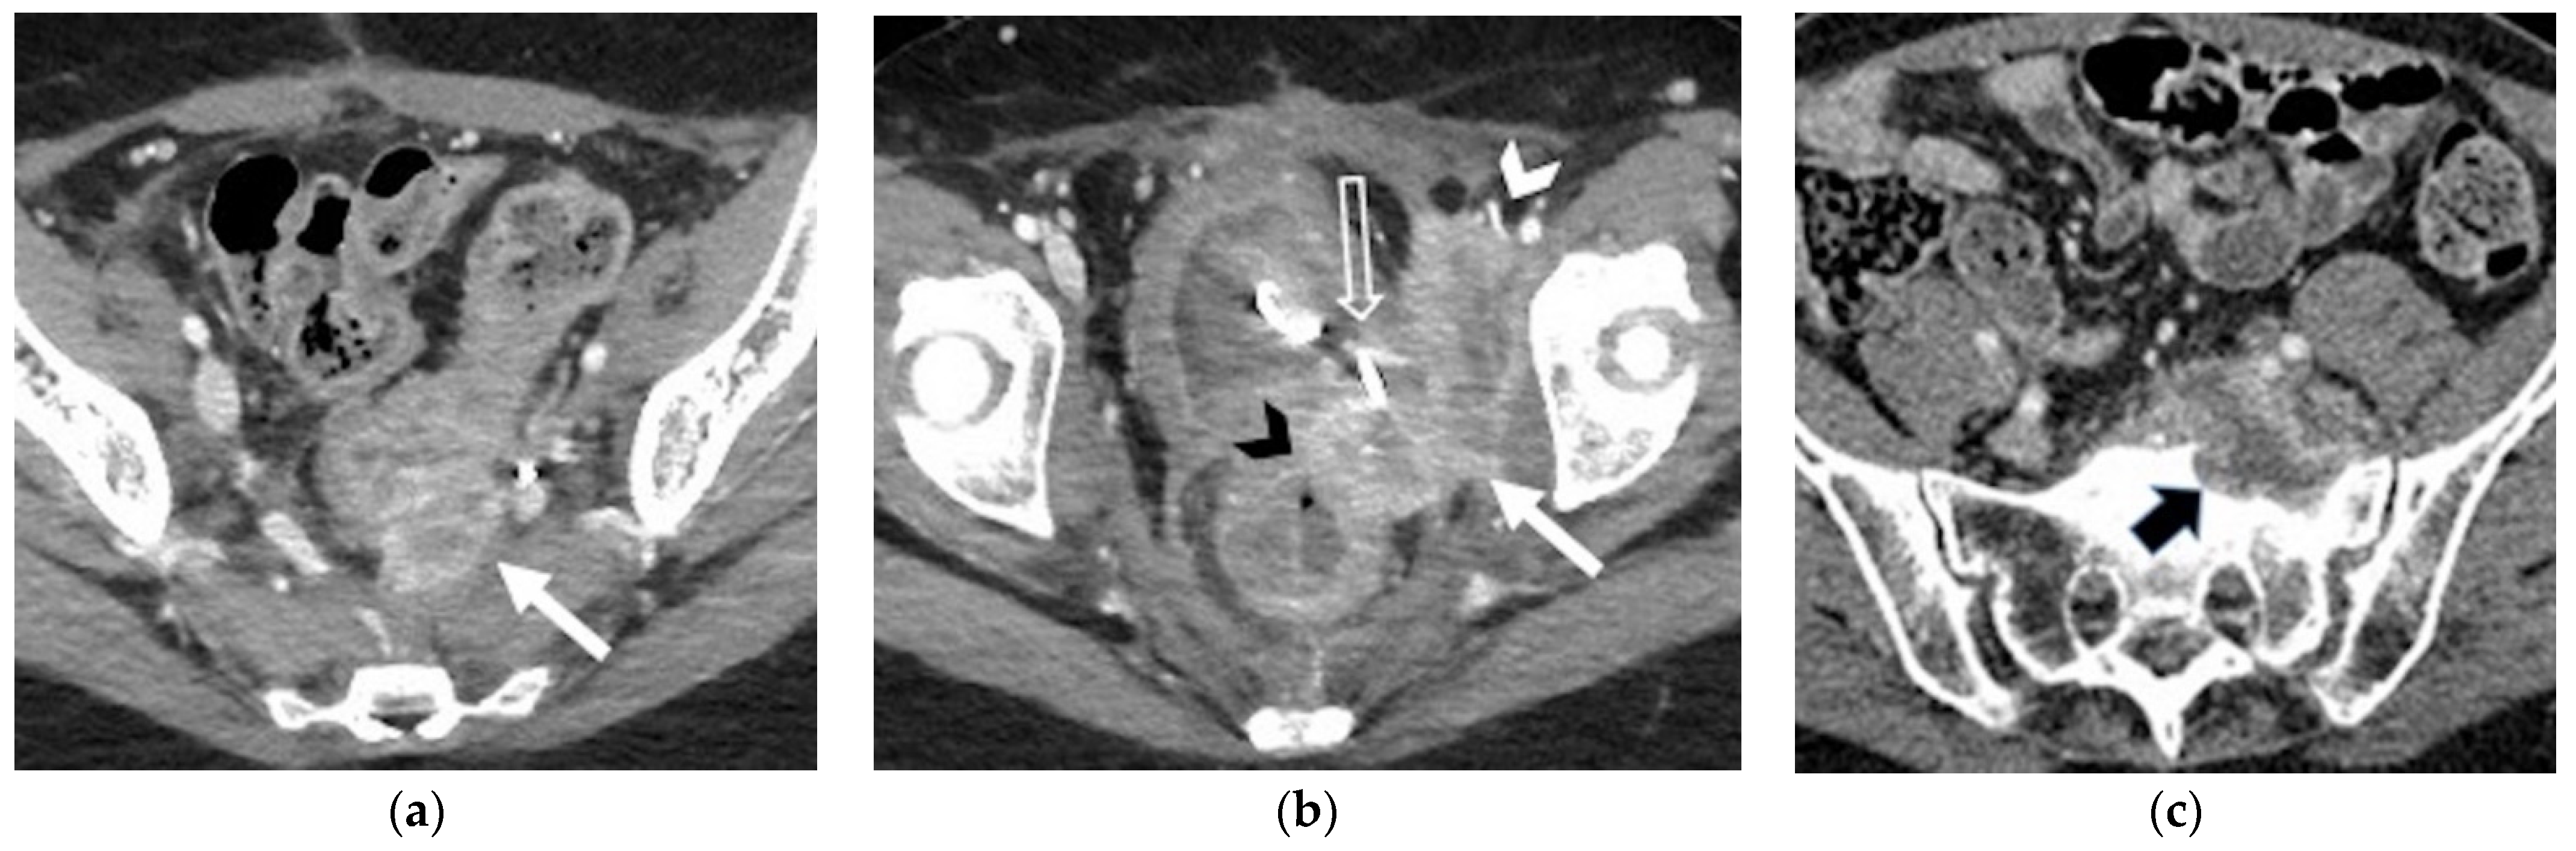

| Distant | |

| Supra-diaphragmatic lymph nodes |

|

| Abdominal and extra-abdominal recurrence |